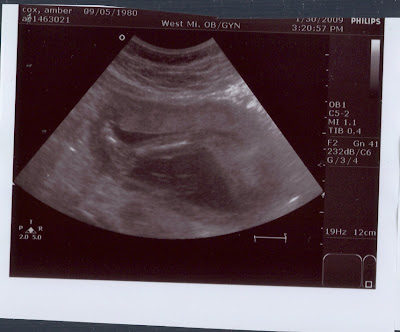

This has been an incredible day! Ryan and I went in for our ultrasound and are thrilled to announce that we are going to have a healthy baby! Praise the LORD!! Here are a few fun shots for you to enjoy/decipher.

To be completely honest, lots of times the ultrasound technician would say things like, "oh, there's an arm" and I would cock my head to the right and really try to see that arm...but I had no idea what I was looking at. Check out the little praying arms in this pic!